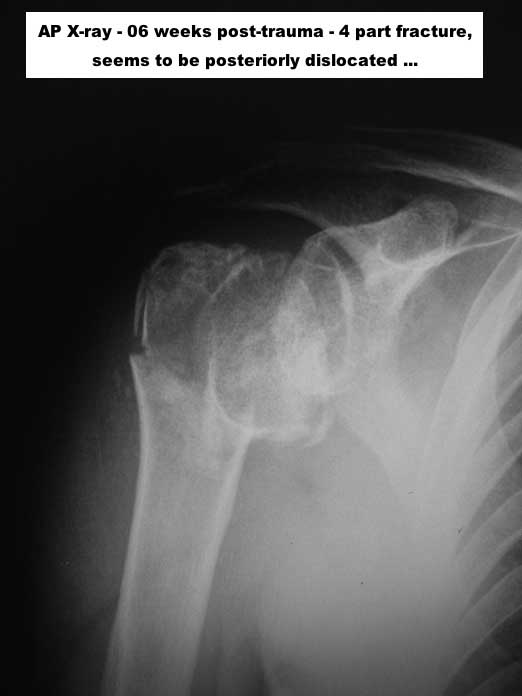

1) This a chronic, 4-part anterior fracture dislocation. How do I know it is anterior, and not posterior, only with a plain AP X-ray ??

Because posterior dislocations do not behave this way, radiographically, believe me. Also, there MAY be an A-C TYPE V dislocation in this shoulder ... But. let's forget that, now ...

Well, the patient is a young female, 26 years, who, unfortunately, had this severe problem NOT properly diagnosed.

6) There is a lot of "heterotopic ossification" around GT, to get things more difficult ...